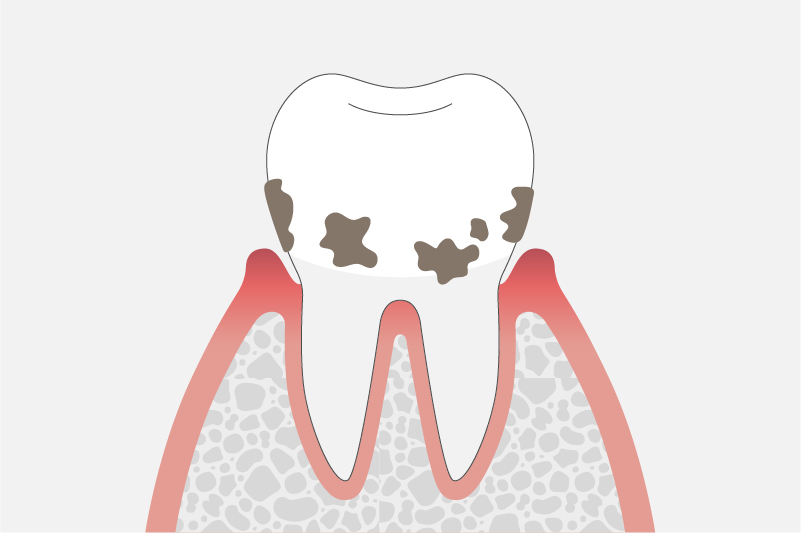

中等度歯周炎

(歯周ポケットの深さ5~7mm)

歯を支えている歯槽骨が1/3~2/3ほど溶けた状態です。

水がしみるようになったり、歯磨きをすると歯茎から血が出たり、歯茎が腫れたり治ったりの症状を繰り返します。また、歯がぐらぐらと動揺しはじめ、膿が出たり口臭が強くなる場合もあります。